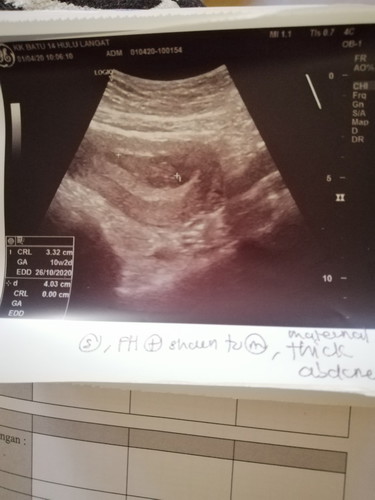

Kenapa bila scan dkt swasta 9 minggu 2 hari Tpi bila scan dkt klinik kesihatan 10 minggu 2 hari ye

Normal sis. Lmbt seminggu atau awal seminggu msh normal. Awl kndungan memng ssh sikit nk tau usia baby.